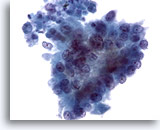

画像 3

肝FNA – 良性肝細胞

核はわずかに大小不同であり、反応性変化を来した肝細胞に典型的な低N/C比を示します。微小な細胞質空胞および細胞質内色素がみられます。

60倍

画像 3

肝FNA – 良性肝細胞

核はわずかに大小不同であり、反応性変化を来した肝細胞に典型的な低N/C比を示します。微小な細胞質空胞および細胞質内色素がみられます。

60倍